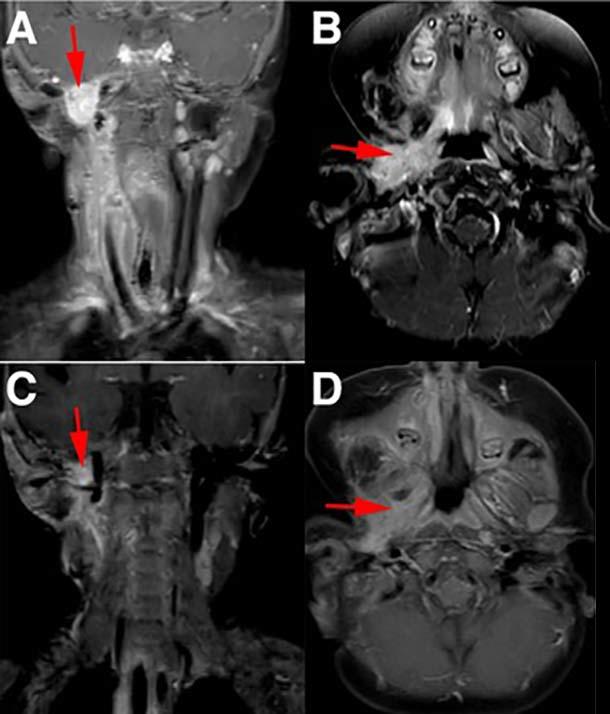

Four MRI images showing before (A, B) and after (C, D) treatment of infantile fibrosarcoma with larotrectinib, demonstrating significant tumor reduction in the neck and oral cavity areas marked with red arrows.

Before (A and B) and after (C and D) MRI images of a child with infantile fibrosarcoma who had a more than 90% reduction in tumors in the neck and oral cavity following larotrectinib treatment.

Credit: Pediatr Blood Cancer. Aug. 2016. doi: 10.1002/pbc.26026. CC BY 4.0

Several children in the initial patient group had infantile fibrosarcoma, which, when it reaches more advanced stages, often requires limb amputations to treat the cancer. In two of the children, larotrectinib shrank their tumors enough that they were able to undergo surgery to remove the remaining tumor without the need for amputation; at the time of patient follow-up, there was no evidence that either child’s cancer had returned.